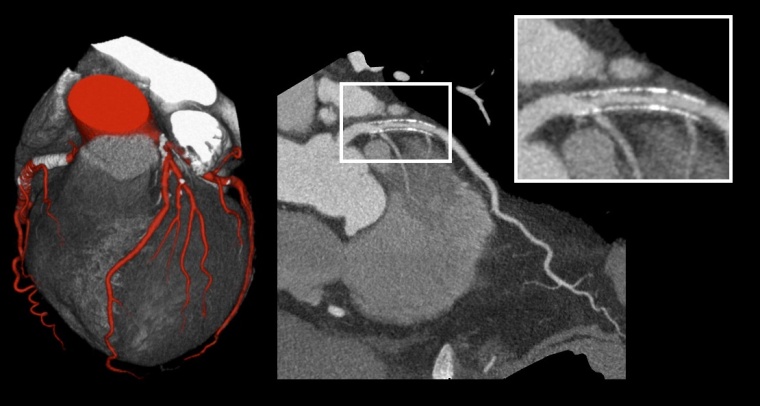

Die Anwendungen der UHR-CT sind vielfältig. In den Bereichen Onkologie, Angiographie, Tumoridentifikation und Verlaufskontrolle kann die neue Auflösung entscheidende Details liefern. Die Darstellung kleinster knöcherner Strukturen, ob bei Frakturen oder knöcherner Hochauflösung im Innenohr wird revolutioniert. Die UHR-Cardio-CT zeigt völlig neue Einblicke in die Koronarien, da Kalzifizierungen wesentlich präziser dargestellt werden können. Die Beurteilung von Stents und Stentlumina bietet eine bisher nicht gekannte Detailgenauigkeit, was die Diagnose entscheidend erleichtern wird. Die Kombination aus Ultra-High-Resolution-CT einerseits und dem Einsatz künstlicher Intelligenz andererseits wird die CT der Zukunft entscheidend prägen.